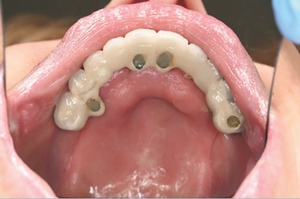

Bone level fixtures were placed in the intraforaminal region with submerged healing, and axially loaded. After alveolar ridge height reduction to facilitate implant placement in the apico-coronal position, one Southern zygomatic implant (Zygex with uniabutment and healing cap) was placed in the left quadrant and three 10mm bone-level implants (021.3310) were placed (UR4, UR1 and UL1 sites) (Figure 6). Two 12mm implants (021.5310)) were then placed in the mandible (LL3, LR2 regions).

A follow-up orthopantomogram revealed that all implants were healing well (Figure 7). The shortened dental arch (SDA) concept was used to restore this patient’s occlusion, and a maxillary bridge and mandibular implant-retained denture were used to restore second premolar to second premolar in each arch (Figures 8 and 9). SDA was introduced in 198114 and is a problem-oriented method that aims to minimise complex restorative treatments.14 It outlines maintaining at least four posterior occlusal units or a minimum of 20 well-distributed teeth to ensure a functional, natural and healthy dentition.15

Careful digital restorative planning enabled a functional and aesthetically pleasing outcome to be achieved with a maxillary bridge and a mandibular implant-retained and -supported denture (Figures 12 and 13). Enhancements in the speed of osseo-integration, the strength of dental implants and the range of prosthodontic materials contributed to the restorative success.